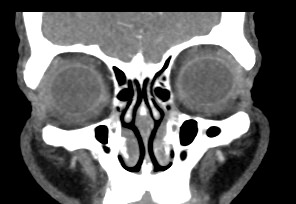

Орбиты (или глазницы) – это костные углубления в лицевом черепе, где расположены глазные яблоки, окруженные жировой клетчаткой, а также слезные железы, слезные каналы, сосуды, нервы, мышцы и связки глаза. Такая небольшая по объему область содержит важные анатомические структуры, обеспечивающие нормальную функцию органа зрения.

Кроме того, область орбиты тесно связана с близлежащими структурами – полостью черепа с расположенным в ней головным мозгом, а также с полостью носа, околоносовыми пазухами и носоглоткой. Различные патологические процессы могут развиваться как в самой глазнице, так и в околоорбитальных структурах, но при этом распространяться на область орбит.

Мультиспиральная компьютерная томография лучше всего визуализирует ткани с высокой плотностью, к которым, в частности, относится костная ткань. Это делает КТ незаменимой при диагностике травматических повреждений глазниц, а также для выявления инородных тел орбит.

На снимках КТ хорошо видны костные структуры глазниц, глазные яблоки, ретробульбарная клетчатка, слезные железы, канальцы, слезные мешки, носослезные каналы.

Мультиспиральная КТ с контрастом позволяет выявить: